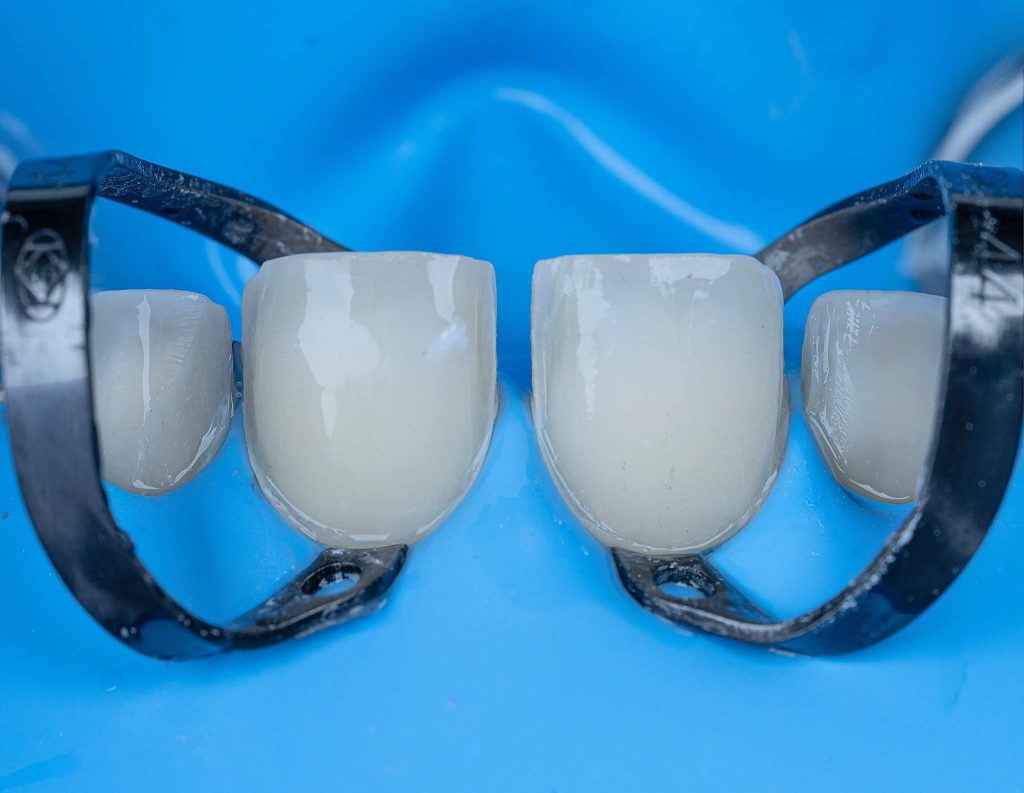

A veneer may be defined as anything that is covering something to improve its appearance. Within dentistry, a veneer is a thin layer of ceramic or composite resin placed on the facial surface of one or more teeth. The thickness can be ranged from 0.3-0.7mm.

The case presented in this case report is for a 27-years-old female patient with a chief complaint of aesthetic correction for her smile. The patient was unhappy with her smile. After clinical examination, there were previous old composite veneering done poorly and incorrectly to close the multiple interdental spacing. After discussing the various treatment options (i.e., orthodontic treatment, direct, or indirect veneers), indirect ceramic veneering was selected. The step-by-step treatment protocol is presented in the images below.

Special thanks to my friend, Dr. Ali Al-Qrimli the CEO of Digital IDEA dental lab for fabrication of the ceramic veneers and the digital designing, with many thanks for the dental ceramist, Dt. Ali Kadum who did the ceramic build-up for this case.